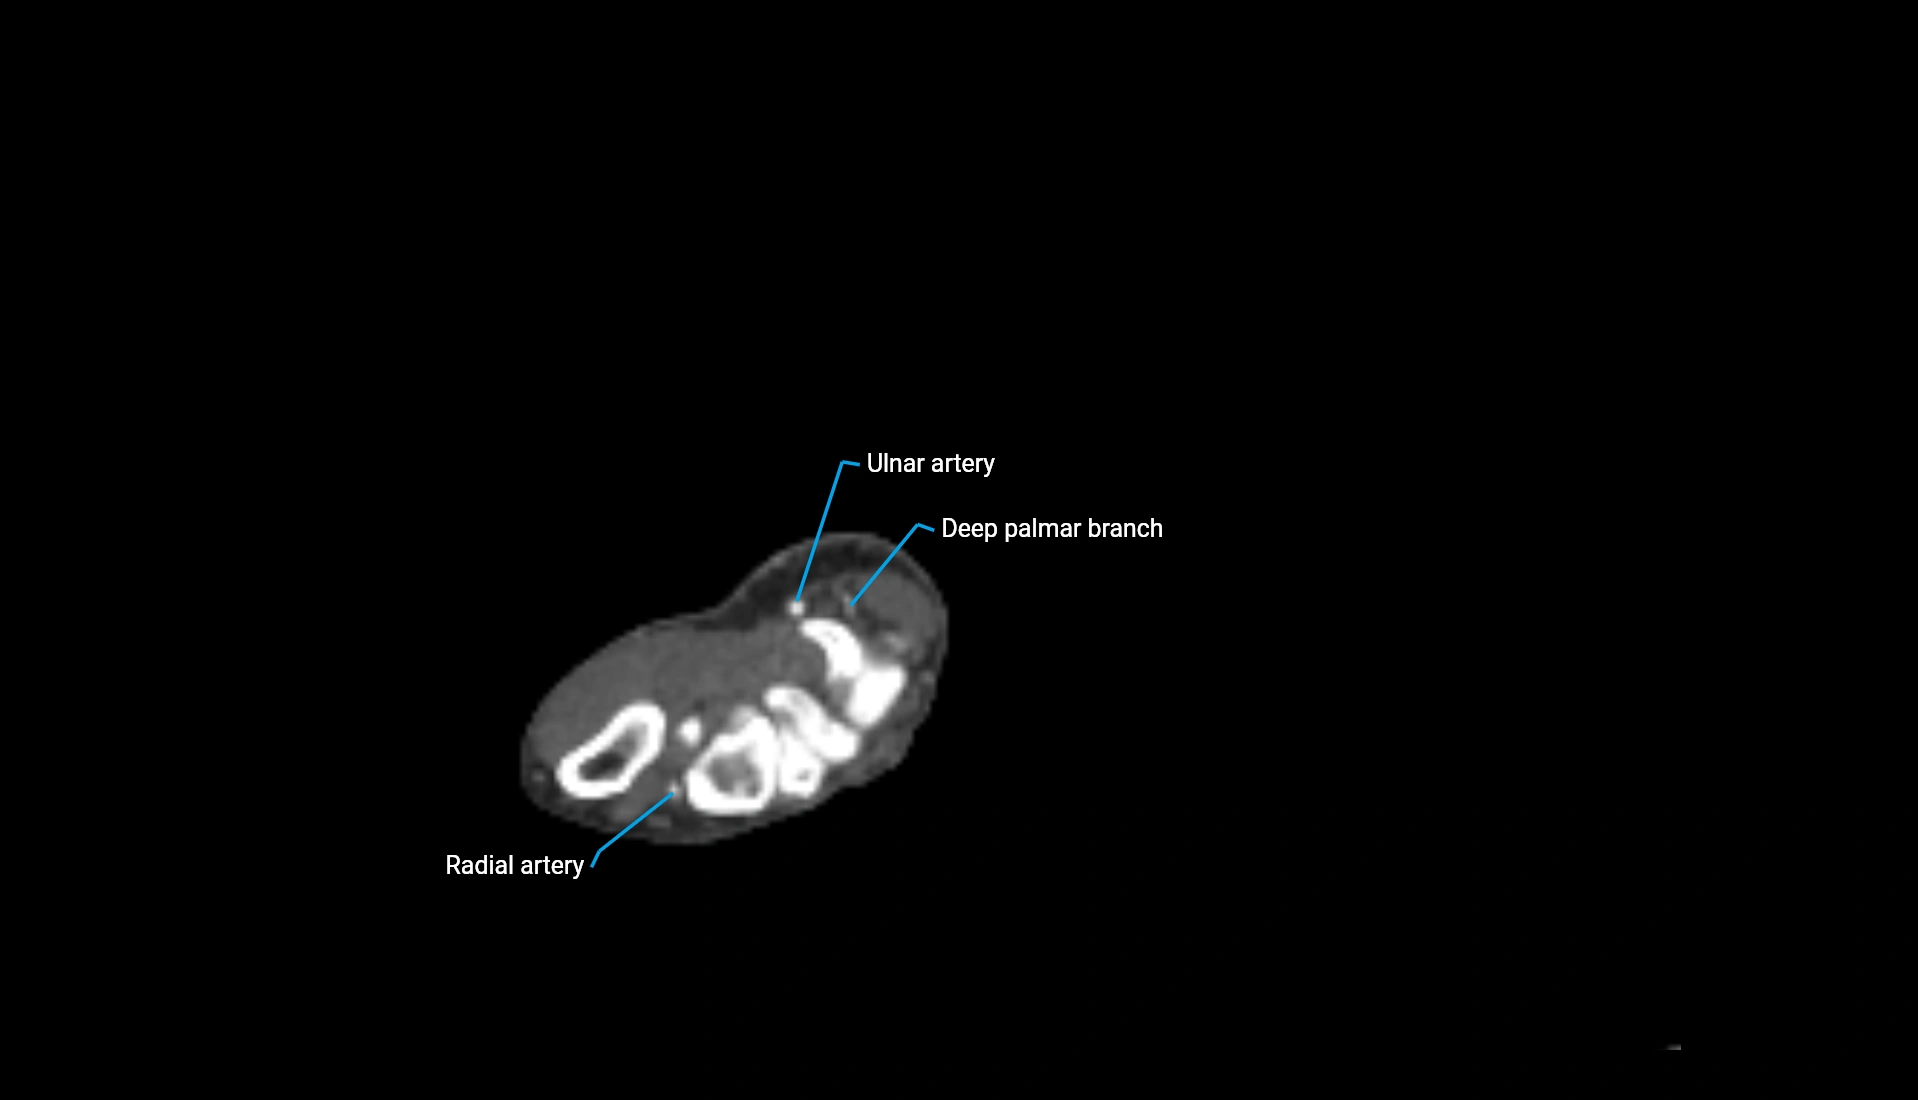

CT Appearance

Non-Contrast CT:

• Cortex: High-density, sharply defined

• Subchondral bone: Dense cancellous matrix

• Articular surface: Smooth concave contour articulating with the capitellum

• Excellent for evaluating bone integrity, alignment, and subtle fractures